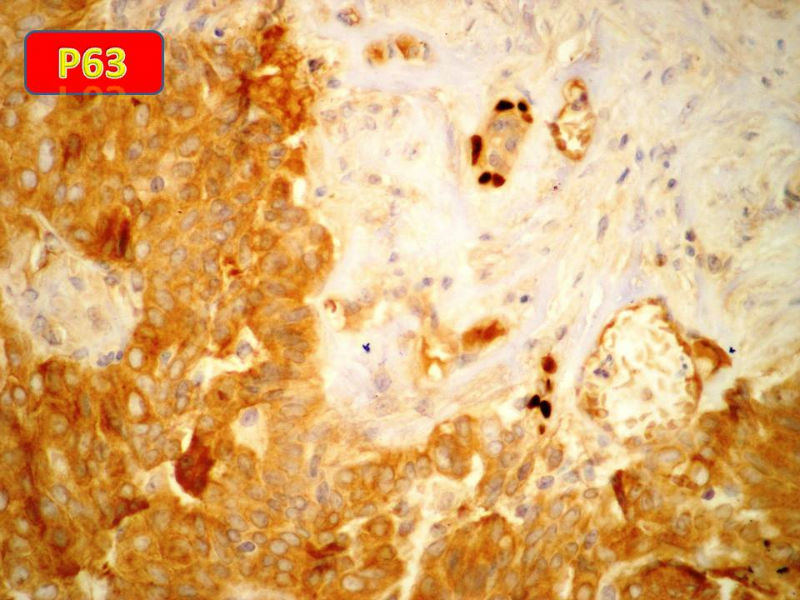

只能说是乳头状瘤

是不是导管内

乳头状瘤 and 导管内乳头状瘤 are the same; Benign lesion.

After you work up and you still cannot be sure it is benign , atypical or maignant lesion, you can call 乳头状lesion.

If this is excisonal case, you should figure out the nature of the papillary lesion.

我的意思就是提醒大家 在不是很确定的情况下 尽量少给自己套枷锁